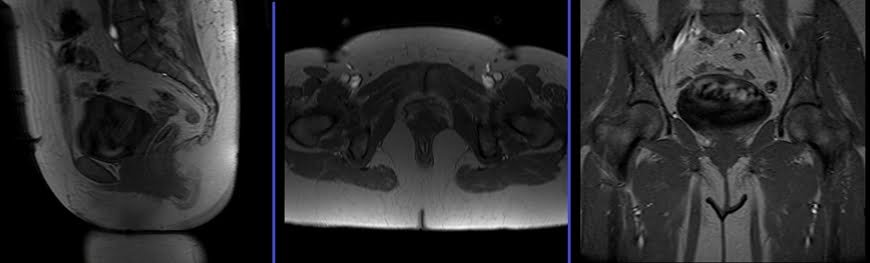

MRI Female Urethra scan localiser

Take a three-plane localizer at the beginning to localize and plan the sequences. Localizers are usually completed in less than 25 seconds, and they are T1/T2-weighted low-resolution scans. Take additional localizers if needed.